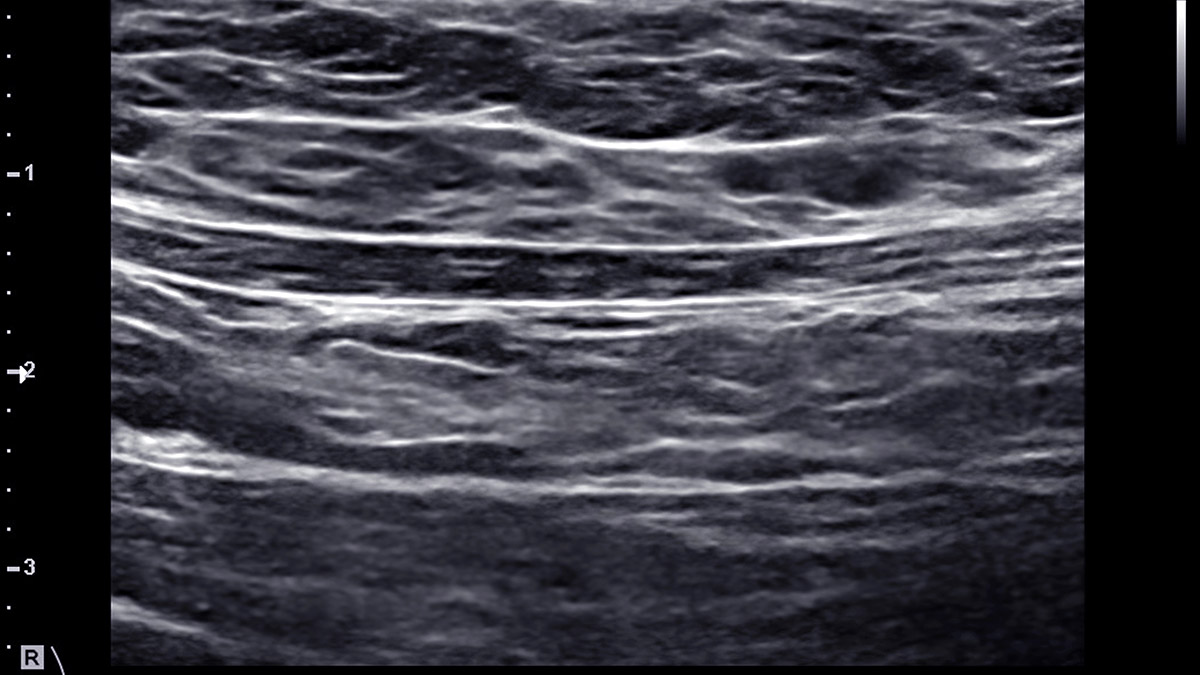

Współczesna kosmetologia estetyczna coraz częściej sięga po technologie, które jeszcze niedawno były domeną medycyny. Ultrasonografia, znana głównie z diagnostyki organów wewnętrznych, zyskuje dziś status jednego z najważniejszych narzędzi zwiększających precyzję i bezpieczeństwo zabiegów. Pozwala specjalistom zobaczyć to, co niewidoczne gołym okiem. To inwestycja, która zmienia standardy pracy w gabinecie i buduje zaufanie klientów.